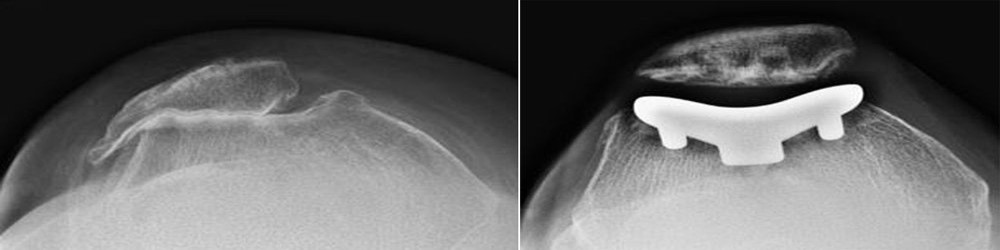

Patellofemoral replacement is a type of partial knee replacement in which only a portion of the knee is resurfaced. The procedure is an alternative to total knee replacement for patients whose damaged bone and cartilage is limited to the underside of the patella (kneecap) and the channel-like groove in the femur (thighbone) that the patella rests in.

Knee cap replacement, also known as patellofemoral replacement, is a surgery to replace the knee cap with a metal or plastic implant. The knee cap is the small, round bone that sits at the front of the knee. It protects the knee.